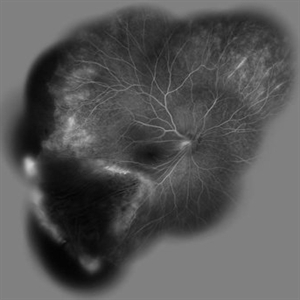

Behcet's Disease Behcet's DiseaseMar 13 2013 by Hamid Ahmadieh, MD Wide field FA of the right eye of a 23-year-old man with retinal vasculitis and branch retinal vein occlusion (BRVO) due to Behcet's disease . Photographer: Solmaz Shahmohammad, Negah Eye Center, Tehran Imaging device: Heidelberg Spectralis Condition/keywords: branch retinal vein occlusion (BRVO), retinal vasculitis